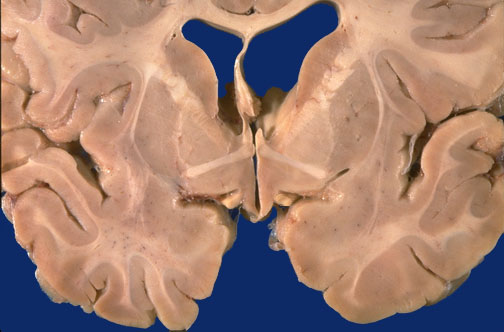

Identify the following regions of the normal brain by clicking in the image below:

Septum Pellucidum - Anterior Commissure - Internal Capsule - Putamen - Globus Pallidus - Caudate Nucleus - Amygdala - Optic Tract